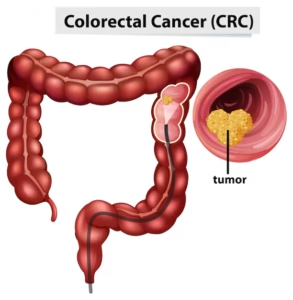

Colorectal Cancer

PET scans for colorectal cancer detect primary tumors, assess lymph node involvement, and identify metastases, particularly in the liver and lungs. They are used in staging the disease, planning surgery or radiation therapy, and monitoring for recurrence.